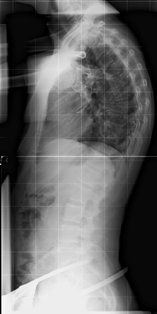

Heute Morgen habe ich mal ein Bild ohne Korsett gemacht. Ich hatte das Korsett allerdings noch nicht so lange davor ausgezogen. Ich meine schon, dass sich bei mir etwas geändert hat. Ich gehe auch weiterhin 1 x Woche zur Krankengymnastik. Zu Hause mache ich allerdings keine Übungen mehr. Ein Vergleichsbild mit Rundrücken habe ich leider nicht. Deswegen habe ich nochmals das Röntgenbild ohne Korsett beigelegt.

- Röntgenbild ohne Korsett

- _Kyphose71° ohne Korsett.jpg (25.26 KiB) 21547 mal betrachtet